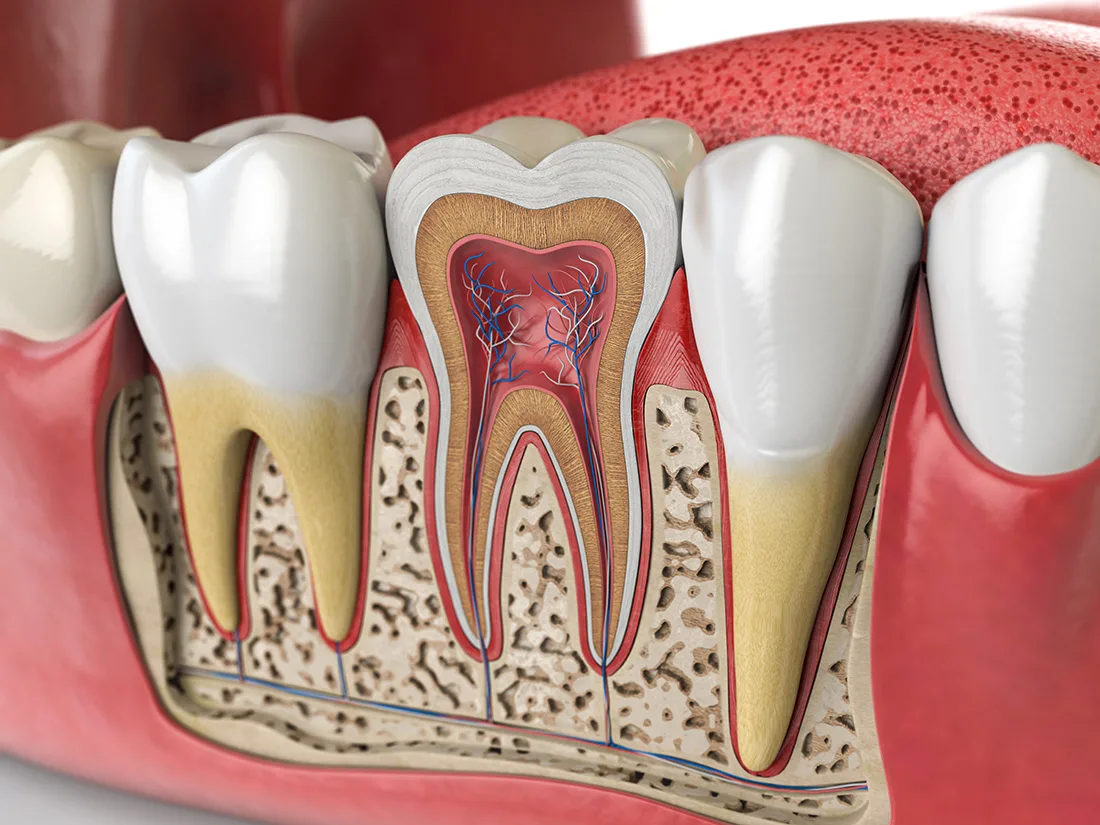

Removing Decay & Infected Pulp

Once you're fully numbed and comfortable, your dentist will begin the process of removing decayed or infected material. They'll start from the outermost layer of enamel and work their way towards the inner pulp. After removing the infected pulp, the canals will be thoroughly cleaned and flushed with a specialized disinfectant to eliminate any remaining infection.

Filling & Sealing

After cleaning and disinfecting your tooth, your dentist will fill the inner cavity with a rubbery substance called "gutta-percha". This inert material provides support to the tooth and replaces the removed pulp. Following this, your dentist will determine whether to restore the tooth with a filling or a dental crown. This decision is based on the extent of decay and the amount of healthy enamel remaining on the tooth.